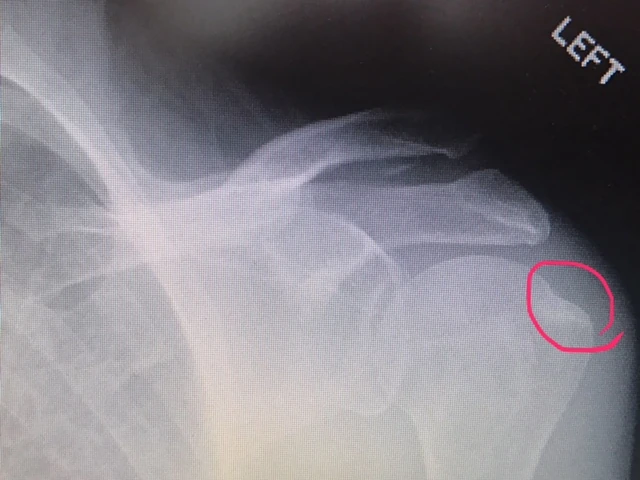

Anyway, I have a shoulder issue, that, I hope, isn’t going to turn into a major issue. I did an MRI and have torn something like 1 cm or my rotator cuff. On my “good arm”. The orthopedic guy that Stacie found here at Scripps, is super. He called me last night at close to 10 o’clock and talked to me for a while about his thoughts. He is going to look at the MRI scan himself, not just the radiologists’ report and then call me later today.

I have no intention of doing surgery on this shoulder. I did the other one a few years ago and it is a nightmare. Plus, it really still doesn’t work that great. I’m going to try to do rehab and see if I can live with the outcome. If not, then I’ll address that later.

Here are a couple drawings Stacie made for me yesterday, trying to explain what was the matter. I liked them, even though they seemed complicated.